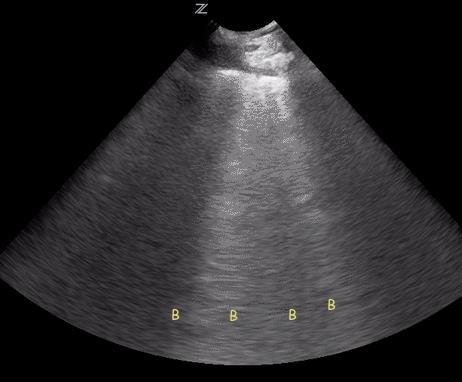

❑ Plan media or visual aids: Decide if whiteboard sketches, imaging reviews, or brief slide visuals will help reinforce key teaching points.